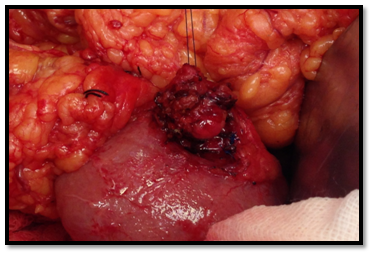

In September of 2014, she underwent a tumour enucleation, without complications (Figure 4). In the postoperative period the patient resolved symptoms and hypoglycaemia did not recur. The histopathological study confirmed a low-grade neuroendocrine tumour with high reactivity to a-chromogranin and synaptophysin (Figure 5A-D). Seven months post-surgery she didn’t present hyperglycaemia or diabetes mellitus.

• Figure 4 Surgery. Tumor enucleation.